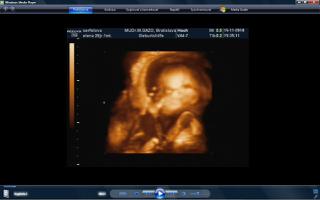

vcera som mala poradnu a teda dopadla pre mna dost prekvapujucu. mala je uz mesiac otocena dolu hlavickou a tlaci sa a tlaci. krcok sa mi zacal skracovat, ale zatial sa neotvara. a aby toho nebolo malo, tak mam aj iritabilnu maternicu. buducu nedelu idem do nemocnice na premeranie krcka a uvidi sa, co bude. aspon, ze ju uvidime 3D potvorku malu nedockavu 🙂 do mesiaca mi zrejme bude treba zaviest pesar.. tooolko radosti naraz a to som povodne vobec nemala mat poradnu, kedze som povodne dosla len s babkou na kontrolu..tak vysetrila aj mna.

caute baby. uz som tu dlho nebola. nejako nestiham. My sme uz boli na tiez na 3D a zase mala mala rucicky pred tvarickou ale daco bolo aj vidno. takze sme zistili, ze sa podoba na muza, teda aspon ten nos usta. Ma skoro 500 g takze je asi o tyzden posunuta neskor.Ak sa mi bude dat tak pridam dake fotky z toho dvd co som vybrala. Inac ja som kupovala tehotenske pancuchy v Brendone v Ba za 4 Eura. teda tenke ale mali tam aj hrubsie a tie stali 15 eur. Ja tiez rozmyslam rodit v ruzinove ale asi skor na Kramaroch. to mam blizsie domov. Ja si doplacam od marca dobrovolne nemocenske poistenie k povinnemu do maximalneho vymeriavaceho zakladu, aby som mala maximalnu matersku. Takze snad s tou materskou sa to bude dat ale horsie to bude s tym rodicovskym prispevkom.